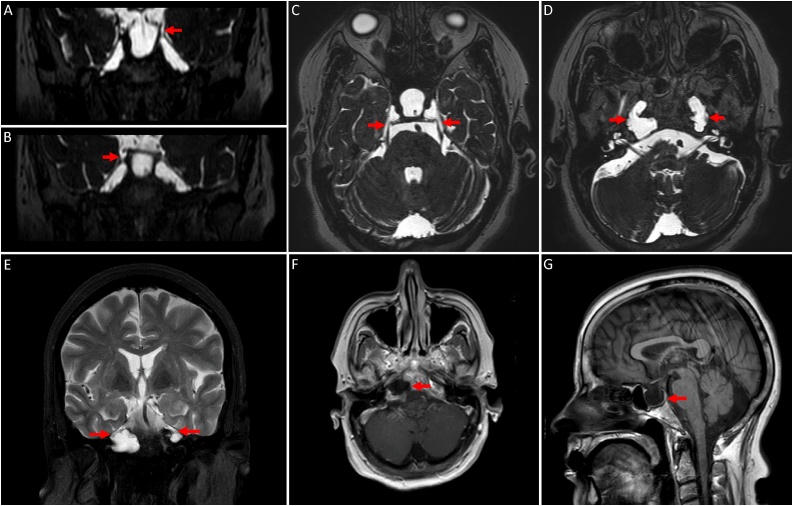

Neuroimaging studies were performed to investigate the possible causes of her headache. The brain MRI showed CSF-containing lesions with no enhancement in the petrous apices bilaterally, communicating with Meckel’s cave (Fig. 1). The non-enhanced CT scan of the brain revealed bilateral osteolytic bony lesions in the petrous apices with fluid density (Fig. 2).

Fig. 1.

MRI of the brain; (A-D) Coronal and axial steady state sequences / FIESTA. (E) Coronal T2 weighted images / T2WI with fat suppression. (F) Axial T1WI post contrast. (G) Sagittal T1WI. (A-F) The images demonstrate bilateral, lytic, expansile, lobular lesions extending from Meckel’s caves into the petrous apices. These lesions follow CSF signal on all sequences with no enhancement. (G) An associated empty sella is noted.